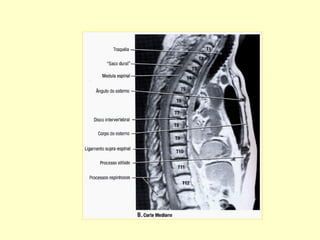

COLUNA CERVICAL PERFIL

Para avaliação da articulação

atlanto-axial por radiografias

convencionais. Realizar incidência

A. P. com boca aberta e perfil.